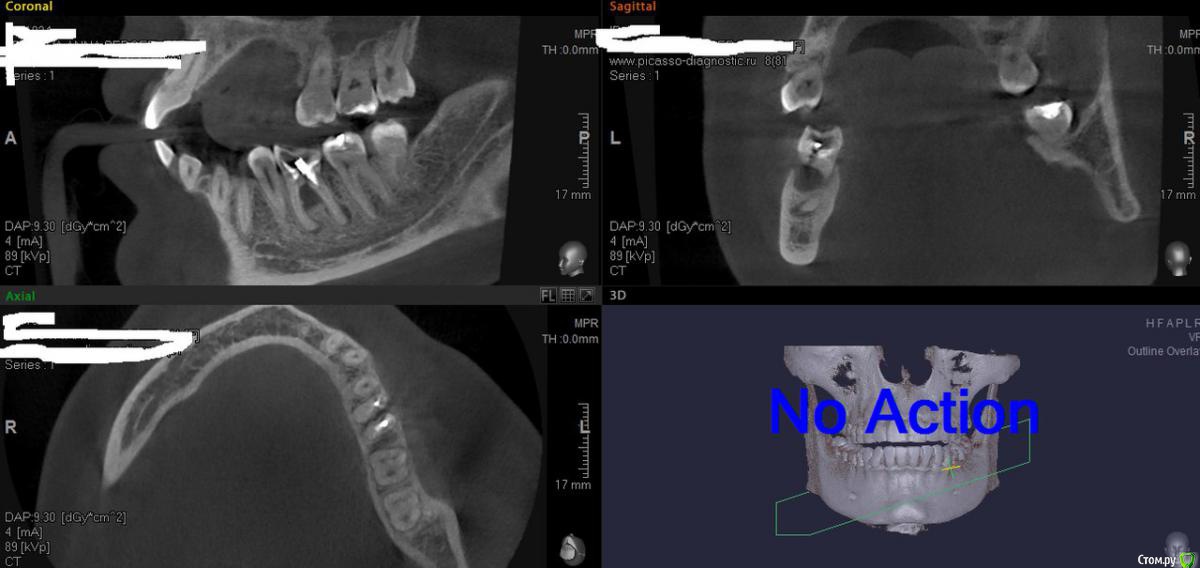

aka_sol Опубликовано 30 сентября, 2015 Поделиться Опубликовано 30 сентября, 2015 Коллеги, здравствуйте!Пациентке планируется удаление зуба. Как поступить? Удаление с консервацией лунки и отсроченная имплантация или все одномоментно с временной коронкой (или хотя бы индивидуализированным формирователем). Сам склоняюсь к 2му варианту, т.к очень хочется сохранить объем десны (внутриротового снимка нет, к сожалению). Спасибо. 1 Ссылка на комментарий

pit Опубликовано 1 октября, 2015 Поделиться Опубликовано 1 октября, 2015 Коллеги, здравствуйте!Пациентке планируется удаление зуба. Как поступить? Удаление с консервацией лунки и отсроченная имплантация или все одномоментно с временной коронкой (или хотя бы индивидуализированным формирователем). Сам склоняюсь к 2му варианту, т.к очень хочется сохранить объем десны (внутриротового снимка нет, к сожалению). Спасибо.jPWqLUoSmhc.jpgЯ б установил одномоментно и завершил ФДМ. Для этого есть все условия: стенки сохранены и расстояние до нерва достаточное чтобы стабилизировать имплантат. Основная проблема в данной ситуации-позиционирование имплантата.Если у вас нет опыта таких операций, я бы рекомендовал удалить и имплантировать через 3-4 месяца. Ссылка на комментарий

колесников Опубликовано 1 октября, 2015 Поделиться Опубликовано 1 октября, 2015 Если ушивать с консервацией, имплантация будет только через 6 мес + не будет хорошего объема прикрепленной десны. Консервация с сдт? Будет прикрепленная десна, но опять же имплантация только через 6 мес.Взникает вопрос "зачем"?Либо просто удаление, либо консервация с одномоментной имплантацией.П.с. Колесников, давайте ваши аргументы за минус моего поста.Аргумент простой-я так уже не работаю и небыло сил вам отвечать ,я поставил минус и тем ограничился. Извините. Если спрашиваете-отвечаю .Все эти советы с выскабливанием двух гранулём и сохранением перегородок это всё так ... Это невозможно. Область от гранулёмы даёт обострение в 90% случаев если оставить только под сгусток. Получаете альвеолит и разрастание грануляций. 1.5-3 недели пациент ходит с болью на перевязки 2-3 раза в неделю. Если говорить про этот случай,на поперечном срезе прекрасно видна резорбция вестибулярной пластинки на 3мм по высоте и ещё 2мм истончённой уйдёт в процессе регенерации. И что получим? Измученного болью и визитами пациента,который через 3 месяца приходит к вам на имплантацию а вы ему говорите: у вас тут двухстеночный дефект,я вам пропишу костную пластику гребня,а потом (через 4 месяца)имплантацию и уже после (если всё будет удачно) мы вам десну нарастим. Где пациент? Убежал пациент. А всего то надо: выскаблить лунку насколько удастся,оставить трихопол в гранулёмы,заполнить лунку кортикальной костью и ушить. Обострение случиться в течении суток-трое,регенерация слизистой в течении трёх недель и на четвёртой спокойно ставите имплант в перегородку. При большом желании можете нанизать сст на формирователь. Вот именно так я поступаю конкретно в таком случае. Не считаю что это правильно. Мне так проще. Пациенту проще. Вы можете использовать другой подход и это будет тоже верно,потому что завершение одно и тоже-замещённый дефект. Спасибо что дочитали. Ещё раз прошу прощения. Ссылка на комментарий